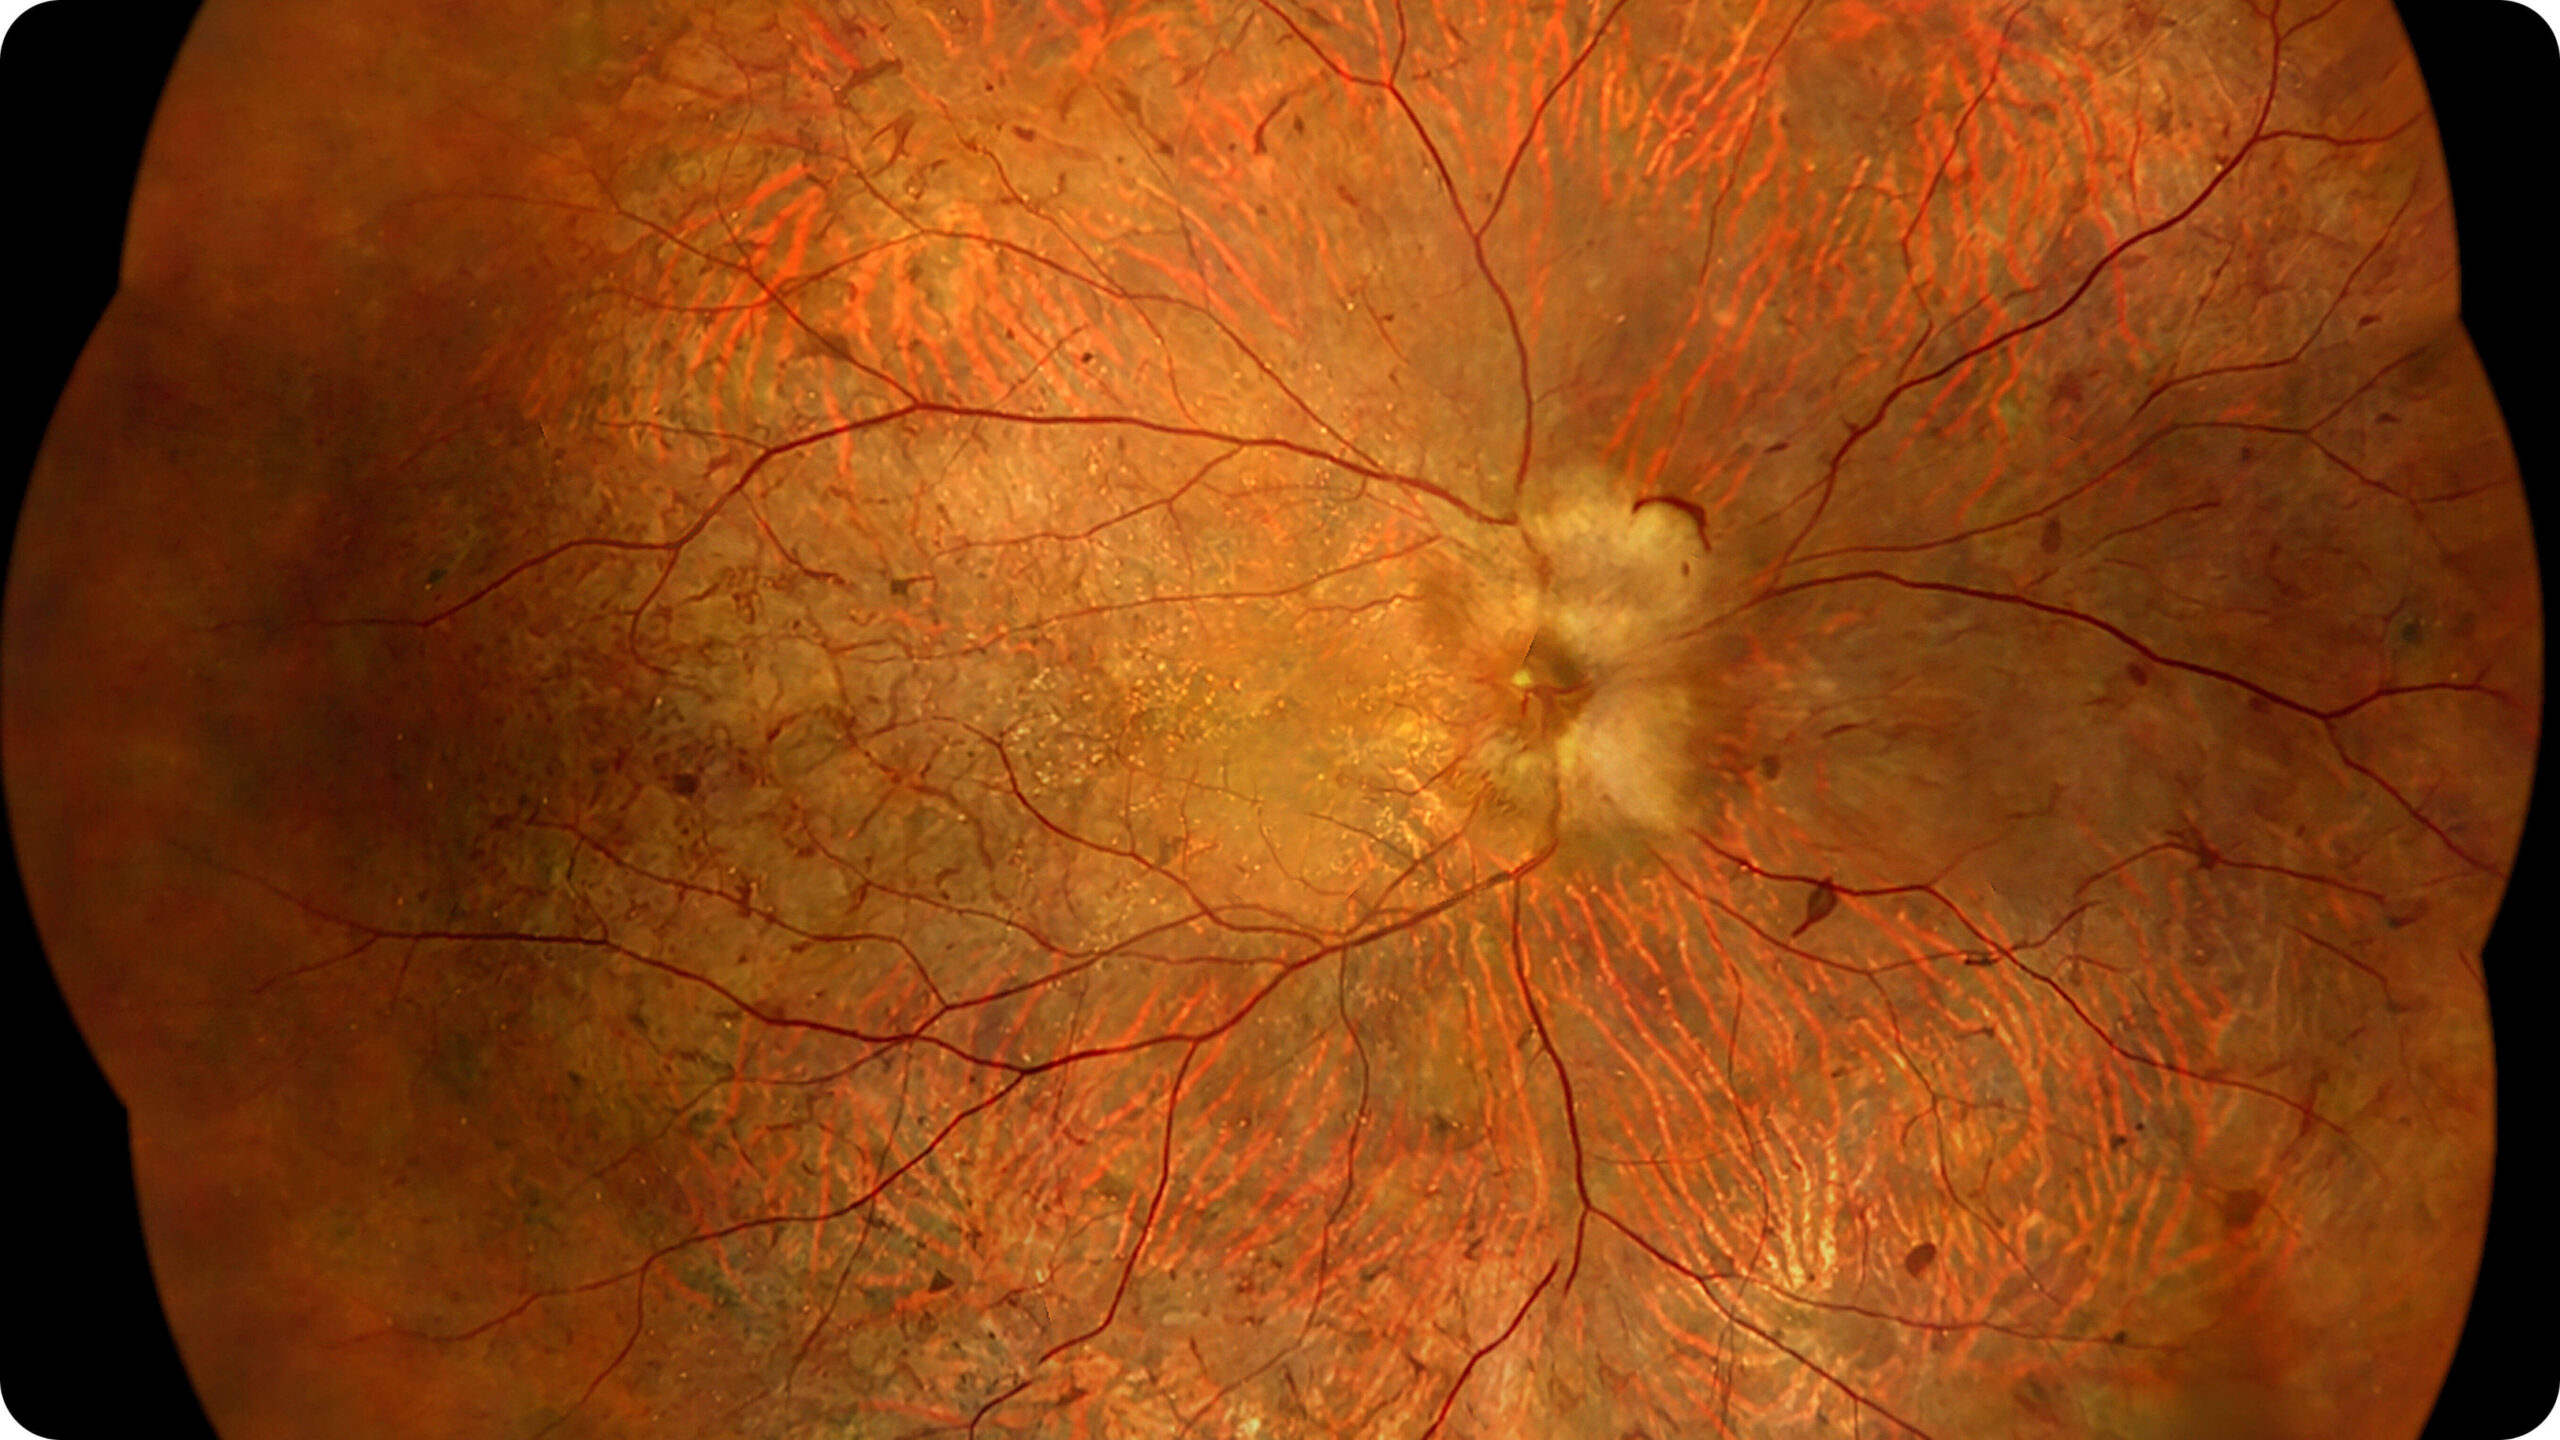

Olho Inteiro

Uma única varredura pode obter rapidamente imagens sincronizadas de imagens coloridas de campo ultralargo/FAF/FFA/ICGA e SS-OCT, alcançando sincronização em tempo real e alinhamento preciso de imagens planas e estruturais da retina, melhorando significativamente a eficiência da inspeção e otimizando o processo de diagnóstico e tratamento.” Uma única varredura pode obter rapidamente imagens sincronizadas de imagens coloridas de campo ultralargo/FAF/FFA/ICGA e SS-OCT, alcançando sincronização em tempo real e alinhamento preciso de imagens planas e estruturais da retina, melhorando significativamente a eficiência da inspeção e otimizando o processo de diagnóstico e tratamento.

Altamente integrado com tecnologias como SLO confocal e SS-OCT, ele combina imagens coloridas SLO de campo ultralargo, angiografia confocal a laser, autofluorescência e imagens tomográficas de segmento anterior e posterior ultraamplas e profundas em um único sistema.

Retinopatia diabética, degeneração macular e outras doenças da retina.

Estudo da coroide em casos complexos.